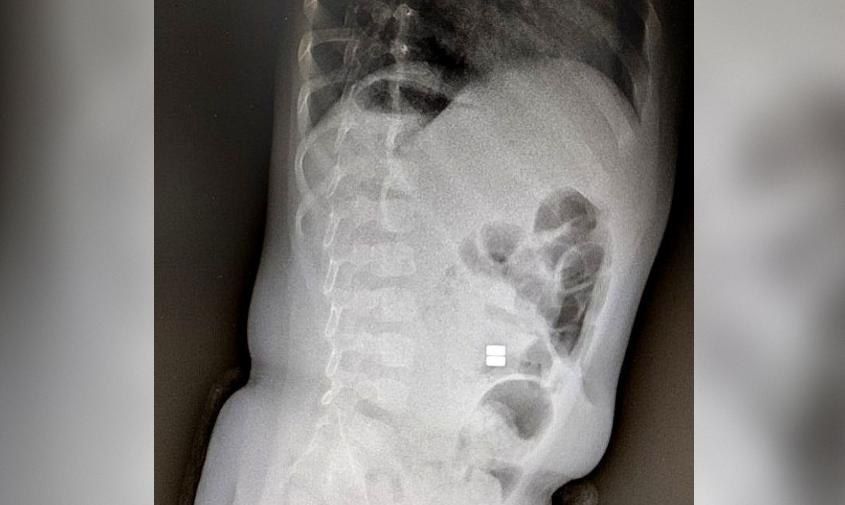

Ежедневно в Детскую областную больницу привозят детей с инородными телами.В Приамурье участились случаи обращений, связанных с проглатыванием детьми магнитных шариков. Подобные ситуации влекут за собой необратимые последствия для здоровья. Возраст...

Врачи бьют тревогу: маленькие амурчане все чаще попадают на операционный стол, проглотив магнитные шарикиАмурские медики бьют тревогу: дети все чаще глотают магнитные шарики. В группе риска — малыши от полугода до трех лет. Врачи...